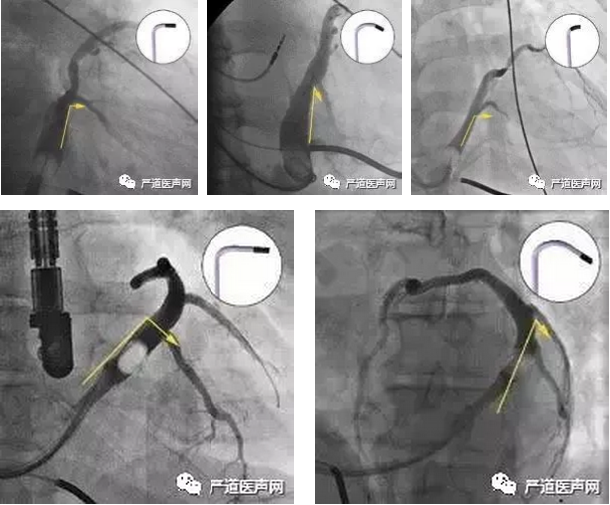

52岁女性患者,因劳力性气促2年,加重3天入院。查体BP 87/53mmHg,双肺可闻及湿罗音,心界向左扩大,心率120次/分。心电图示心房扑动,LBBB(QRS时间0.15s),室性早搏。心脏彩超示Lvd 59mm,EF 20%。诊断为扩心病,房扑,全心衰,心功能III-IV级。符合CRT-D适应证。手术要点:尝试多种方法寻找冠状窦口失败,考虑冠状窦畸形,从股静脉顺利置入冠状窦电极导管,保留下肢冠状静脉窦的电极,指引导丝至下腔静脉,电极顺利进入冠状窦。

23.jpg

24.jpg

25.jpg

术中影像